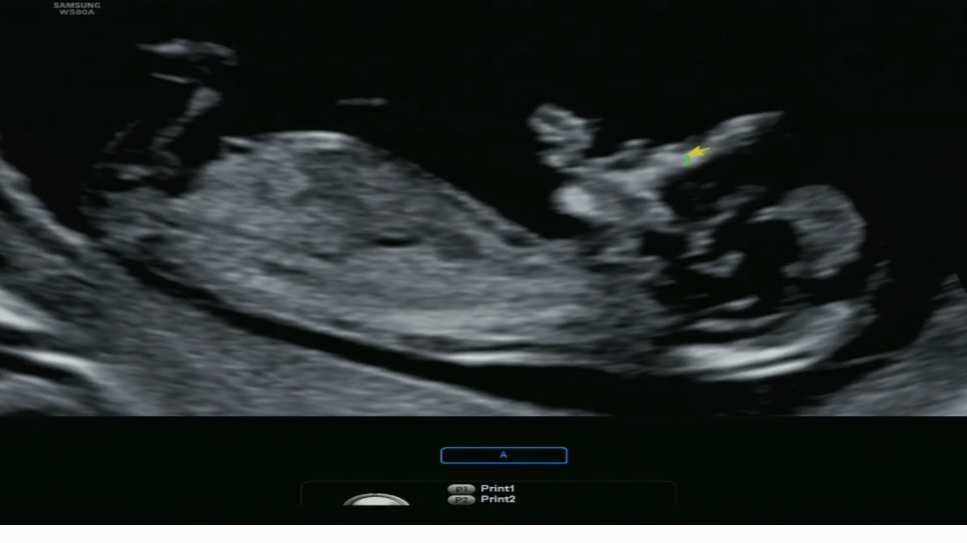

12주 초음파 사진입니다. 지인들에게도 챗GPT에도 묻고 요즘 아주 흥미롭게 답변들을 기다리고있어요 ㅋㅋㅋㅋㅋ 고수님들 한번만 봐주세요